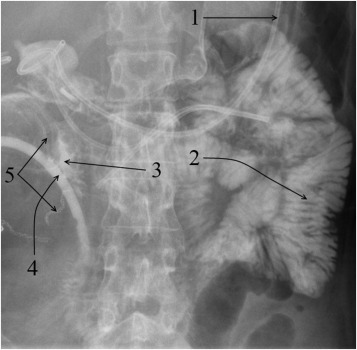

One patient (Patient 14) was diagnosed with partial nonocclusive thrombosis of both portal vein (up to 75% of the lumen) and splenic vein of the graft, and one patient (Patient 28) developed distal thrombosis of the transplant splenic vein. Ultrasound screening identified thrombosis of the upper mesenteric artery of the transplant in five patients (Patients 21, 34, 36, 37, and 39). This was subsequently confirmed by computed tomography (Figure 1).

Abdominal computed tomography (Patient 34): (1) aorta; (2) common iliac artery; ...

Abdominal computed tomography (Patient 34): (1) aorta; (2) common iliac artery; (3) internal iliac artery; (4) external iliac artery; (5) pancreas transplant Y-graft; (6) filling defect in the region of the superior mesenteric artery of the pancreas transplant; (7) splenic artery.